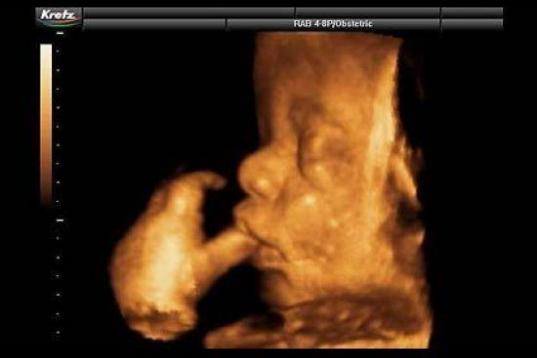

En esta galería puedes ver en fotos como es el desarrollo de un feto de semana en semana:

Desarrollo del feto, en fotos